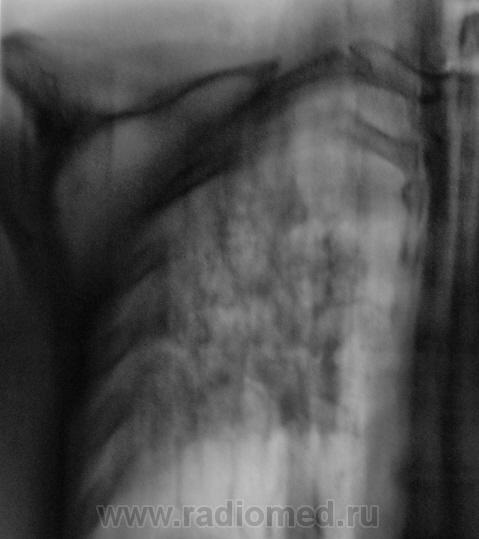

Людмила Григолрьевна, но тут, то процесс двусторонний, хоть преимущественно правосторонний. А на полноформатных изображениях (томограммах), и очаги справа в среднем и нижнем легочных полях дифференцировались.

Вот, и мы так решили, с учетов ограничеснных возможностей нашей ЦРБ-ушки. Взял коллега фтизиатр "изображения", а также и изображения в динамике, а также необходимый "гарнир", и поехал в головное "фтизное" учреждение. В учреждении проконсультировали и выставили правосторонний инфильтративный. Ну и у нас считай - гора с плеч...

Пациента госпитализировали в областное противотуберкулёзное учреждение. Пролечили в течение месяца.... и выписали.

Произведен контроль после лечения. Заключение рентгенолога данного учреждения - "Со стороны органов грудной полости патологических изменений не выявлено".